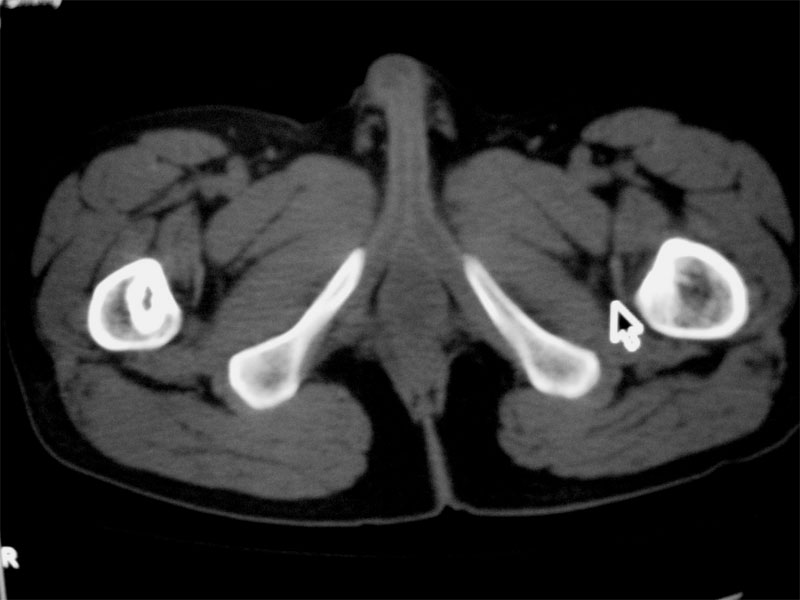

标题: CT16604:男32岁,左髋关节处疼痛月余 [打印本页]

标题: CT16604:男32岁,左髋关节处疼痛月余

左侧髋关节少量积液.上传骨窗

建议提供骨窗资料

考虑左股骨头缺血性坏死;右股骨上段良性骨肿瘤,考虑成软骨细胞瘤可能。建议上传骨窗。